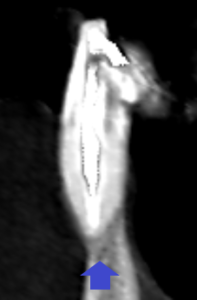

冠状断のCT画像の青い矢印の歯の歯列矯正治療後の矢状断のCT画像です。

根の先は歯槽骨内にありますが、大きな膿の影がみられました。